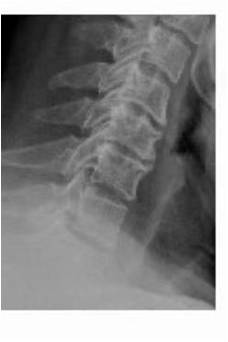

术后 图片1

术后 图片2